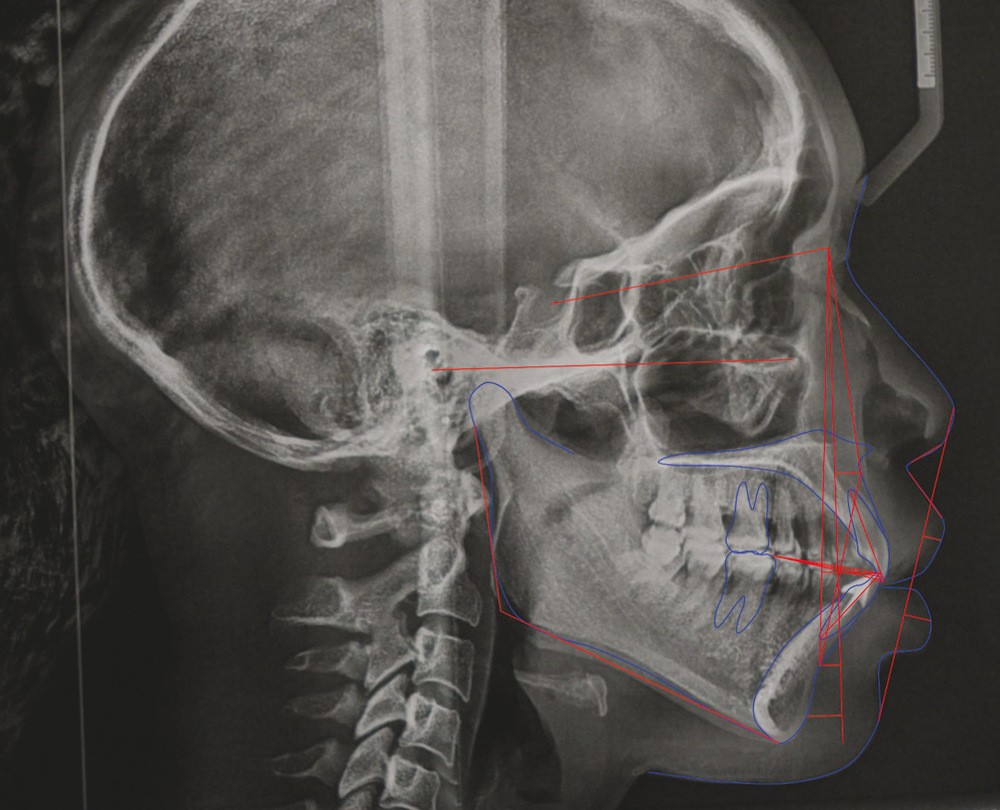

L’analyse céphalométrique de profil révèle des rapports de classe II de Ballard par prognathie maxillaire sur un schéma facial normodivergent associés à une forte proalvéolie mandibulaire (IMPA : 108°) et une légère retroalvéolie maxillaire (I/FH : 108°) (fig. 9 et 10).